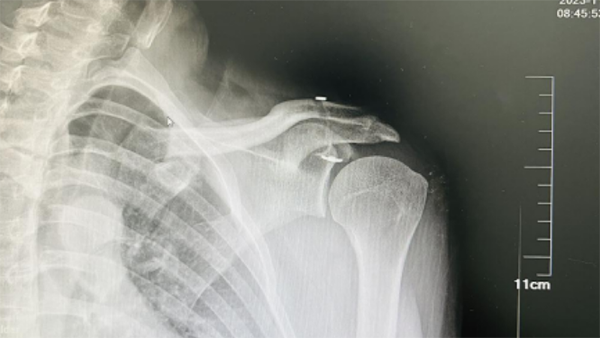

图片3.png

(肩关节镜下肩锁关节脱位可调节带袢钢板内固定术后,内固定Endobutton位置良好。)